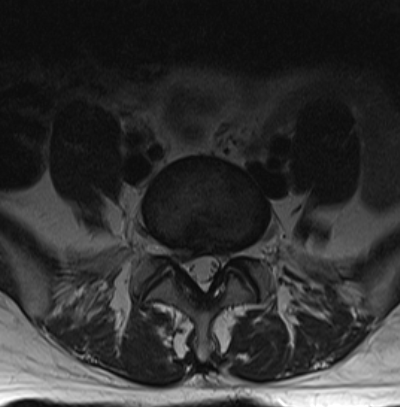

La paciente fue intervenida con un abordaje posterior medial (incisión de 3-4 cm) y con técnica microquirúrgica se realizó una discectomía L5-S1 derecha, preparación de disco y colocación de prótesis intersomática de titanio asociada a fijación transfacetaria. Obsérvese en la imagen anterior la adecuada alineación de facetas así como una adecuada amplitud de las mismas para realizar una fijación transfacetaria bilateral. En el caso que hubiésemos tenido que quitar mucha faceta ipsilateral o esta se hubiese fracturado, habríamos completado la fusión con dos tornillos transpediculares.